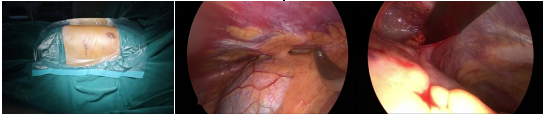

手术中体位,矫形器置入过程

手术前后对比及伤口情况